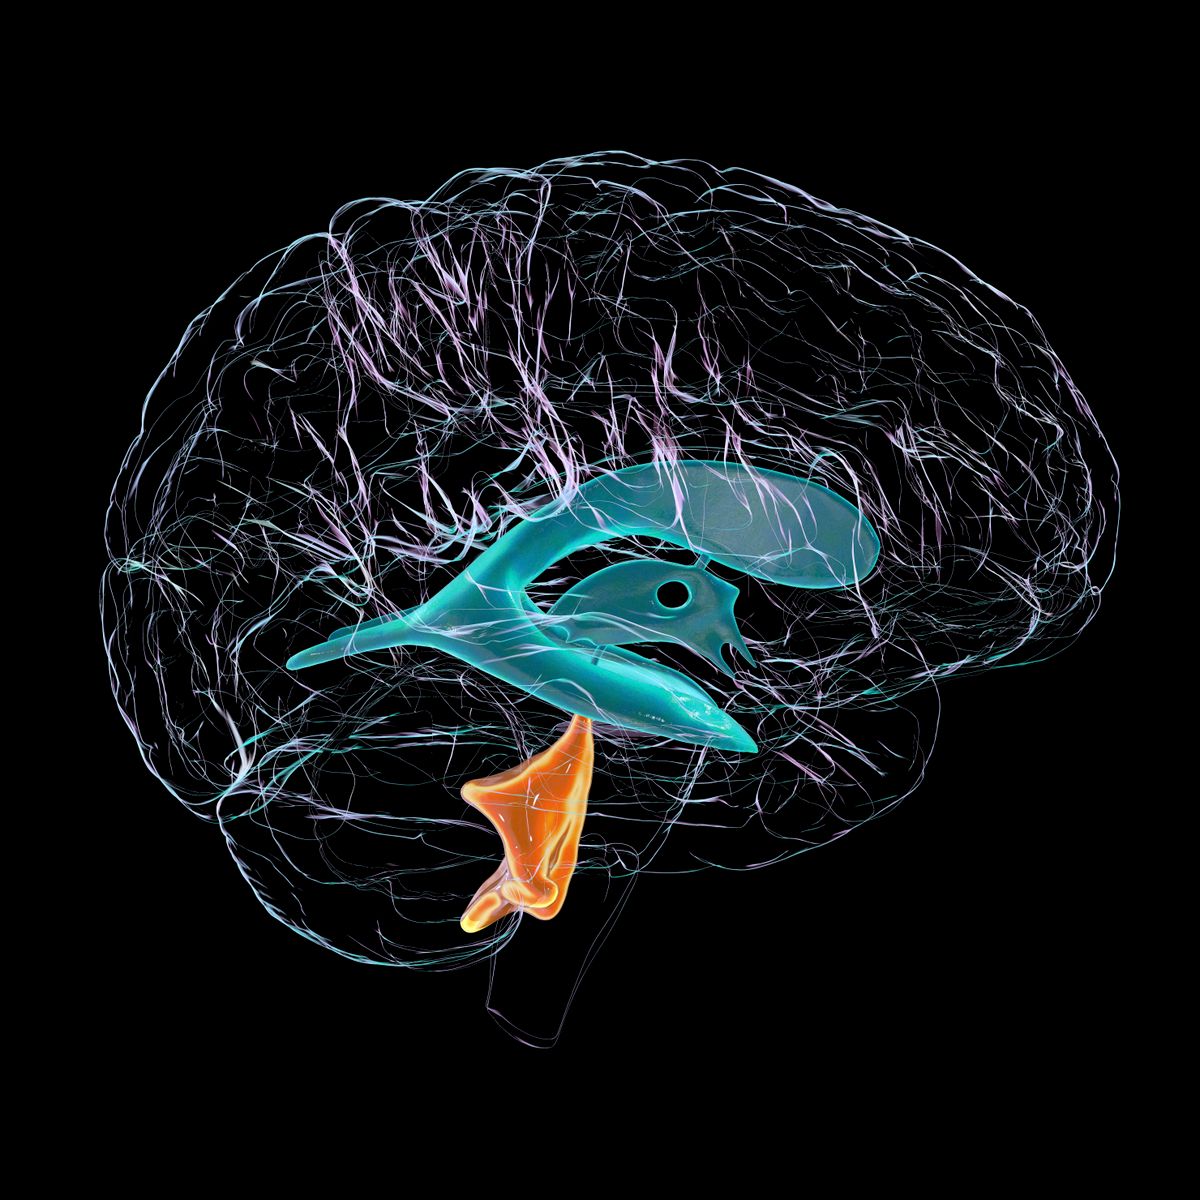

Lucas egészen pontosan diffúz belsőpontin-gliómában (DIPG) szenvedett, amely egy évente néhány száz gyermeket érintő ritka, de halálos rákbetegség. Bár az utóbbi időben halvány előrelépések látszottak, a DIPG még mindig végzetes, a gyerekek túlnyomó többsége nem éli túl a diagnózist követő egy évet, egy nemrégiben készült tanulmány szerint pedig mindössze 10 százalék a kétéves túlélési arány.

„Egy sor MRI-vizsgálatot elvégeztünk, így végig tudtam követni, ahogy a daganat eltűnik” – nyilatkozta az AFP-nek Lucas kezelőorvosa, Jacques Grill. Ennek ellenére a kezelés hosszú ideig folytatódott, és csak másfél éve állították le, miután a daganat teljesen eltűnt a fiú agyából.

A kutatók most azt próbálják megérteni, hogy Lucas daganata miben tért el a többiekétől. Ehhez a tumor genetikai jellegzetességeit vizsgálják. A kísérletekhez laboratóriumban növesztett, szervhez hasonló szövetstruktúrákat, ún. organoidokat használnak.

Az organoidokkal a szakértők tulajdonképpen Lucas agyát akarják reprodukálni, ugyanazzal a tumorral, és annak genetikai sajátosságaival, amit a fiúban azonosítottak. Ha ez sikerül, az eredmények birtokában a következő lépés egy olyan gyógyszer létrehozása lesz, amely általánosan mindenkinél működni fog.